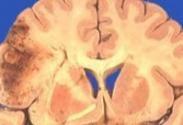

神經元蠟樣脂褐質沉積癥癥

• 神經元蠟樣脂褐質沉積癥

628健康網為您分享有關神經元蠟樣脂褐質沉積癥的癥狀,神經元蠟樣脂褐質沉積癥的治療方法,神經元蠟樣脂褐質沉積癥的預防...